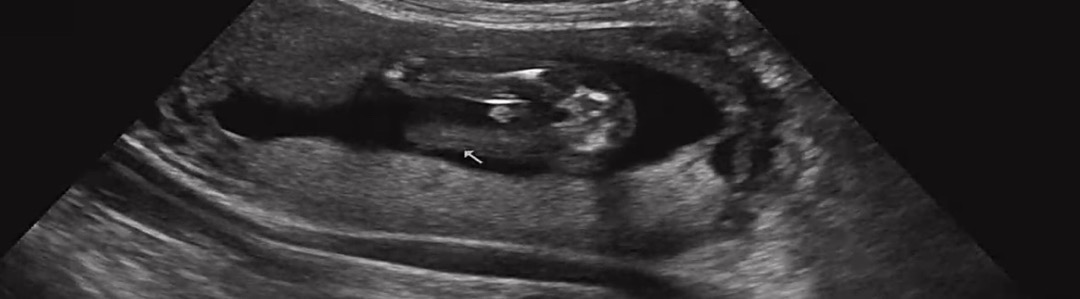

아들인거죠??!

아들같죠??

아들입니다~

아들같아용 ㅎㅎ